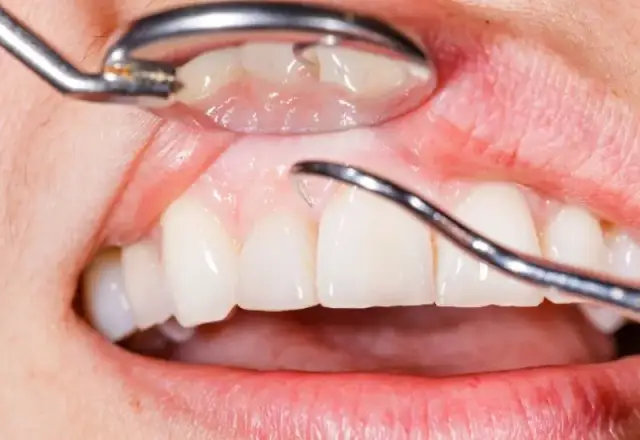

Wizualizacja zmian nowotworowych w jamie ustnej jest kluczowa dla diagnozy raka dziąseł. Zdjęcia raka dziąseł mogą ujawniać istotne cechy, które pomagają lekarzom w ocenie stanu pacjenta. Obrazy te mogą być używane do porównania z innymi przypadkami, co ułatwia postawienie diagnozy. Dzięki zdjęciom można również ocenić postęp choroby oraz skuteczność zastosowanego leczenia.

Ważne jest, aby zwracać uwagę na szczegóły na zdjęciach. Kluczowe cechy obejmują rozmiar, kształt oraz kolor zmian. Na przykład, guzki mogą być twarde i zgrubiałe, a owrzodzenia mogą mieć nierówne brzegi. Zrozumienie tych cech jest niezbędne dla właściwej diagnozy i leczenia. Warto również pamiętać, że zdjęcia powinny pochodzić z wiarygodnych źródeł medycznych, aby zapewnić ich dokładność.

Jak interpretować zdjęcia raka dziąseł – kluczowe cechy

Interpretacja zdjęć zmian nowotworowych na dziąsłach wymaga uwagi na kluczowe cechy, które mogą wskazywać na obecność raka. Przede wszystkim, należy zwrócić uwagę na kształt zmian; guzki powinny być twarde i zgrubiałe, a owrzodzenia mogą mieć nierówne brzegi. Kolor zmian również ma znaczenie – zmiany mogą być białe, czerwone lub ciemnoczerwone, co może sugerować różne stany patologiczne. Ponadto, ważne jest, aby ocenić, czy zmiany są statyczne czy też się rozwijają, co również wpływa na diagnozę.

W przypadku zdjęć, które wykazują cechy zapalne, takie jak obrzęk lub zaczerwienienie, również powinny być brane pod uwagę. Dokładna analiza tych cech jest kluczowa dla postawienia właściwej diagnozy i podjęcia odpowiednich działań terapeutycznych. Warto, aby pacjenci konsultowali się z lekarzem w celu omówienia wszelkich niepokojących zmian, które zauważą na zdjęciach.